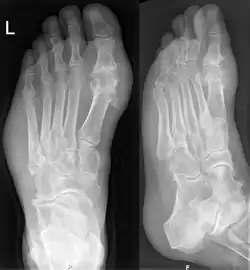

Les radiographies sont normales au début et ne servent qu'à exclure un autre diagnostic. En revanche, elles servent à rechercher les conséquences osseuses ou articulaires de la goutte chronique (arthropathie goutteuse).